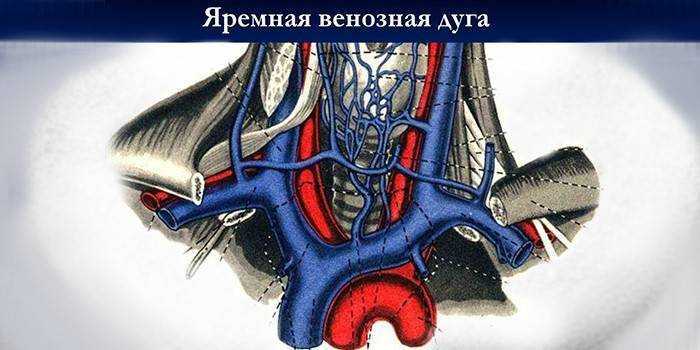

Анатомия внутренней яремной вены: КТ изображения